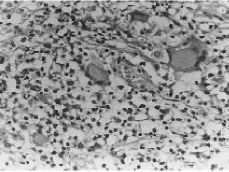

La exploración mostraba una paciente consciente y bien orientada en cuyo abdomen existían varias cicatrices retráctiles de las laparotomías previas. Mediante la palpación abdominal se constataba un abdomen globuloso, no doloroso a la palpación y sin organomegalias. En la exploración ginecológica se apreciaba una vulva con erosiones y ulceraciones redondeadas o rectilíneas de borde violáceo e indurado con fondo rojizo exudativo, aisladas y confluentes que se distribuían por ambos labios, horquilla vulvar, pliegues inguinales, región perianal y surco interglúteo, existiendo pérdida de tejido de forma anular en labio menor derecho (Figs. 1 y 2). En la vagina había un flujo de aspecto candidiásico, sin observarse lesiones, y la pelvis menor estaba libre.

Figura 1. Lesiones vulvares originadas por la enfermedad de Crohn. Erosiones y ulceraciones aisladas y confluentes distribuidas por ambos labios, horquilla vulvar, pliegues inguinales, región perianal y surco interglúteo.

Figura 2. Extensas úlceras vulvares con pérdida de tejido de forma anular en labio menor derecho y formación de puentes cutáneos.